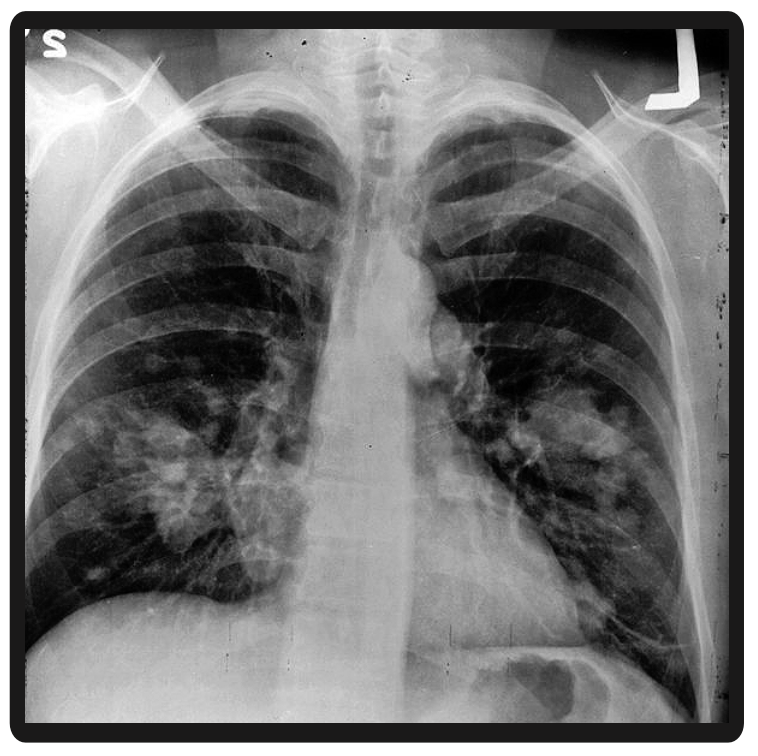

Dataset: The complete WorldMedQA-V includes a total of 726 QAs and 850 images across four countries: Brazil, Israel, Japan, and Spain. Each QA is paired with at least one image, though some images appear in more than one question. After the exclusion of questions with multiple images or correct options, the final evaluation subset contains 568 QAs, each with a single associated image and correct option. Table 2, in Appendix A.3, provides a detailed summary of data distribution across countries and languages. Box 1 in Appendix A.4 shows an example from the Brazilian dataset.

Furthermore, although the benchmark introduces multimodal elements, it pairs only one image per question. Real-world clinical scenarios often involve multiple images from different time points or modalities, such as a sequence of X-rays, CT scans, and pathology slides. Another limitation is that text that is within images were not translated or adapted. English translations, although validated by native-speaking clinicians from each country, require further cross-validations, as these are typically nontrivial tasks.